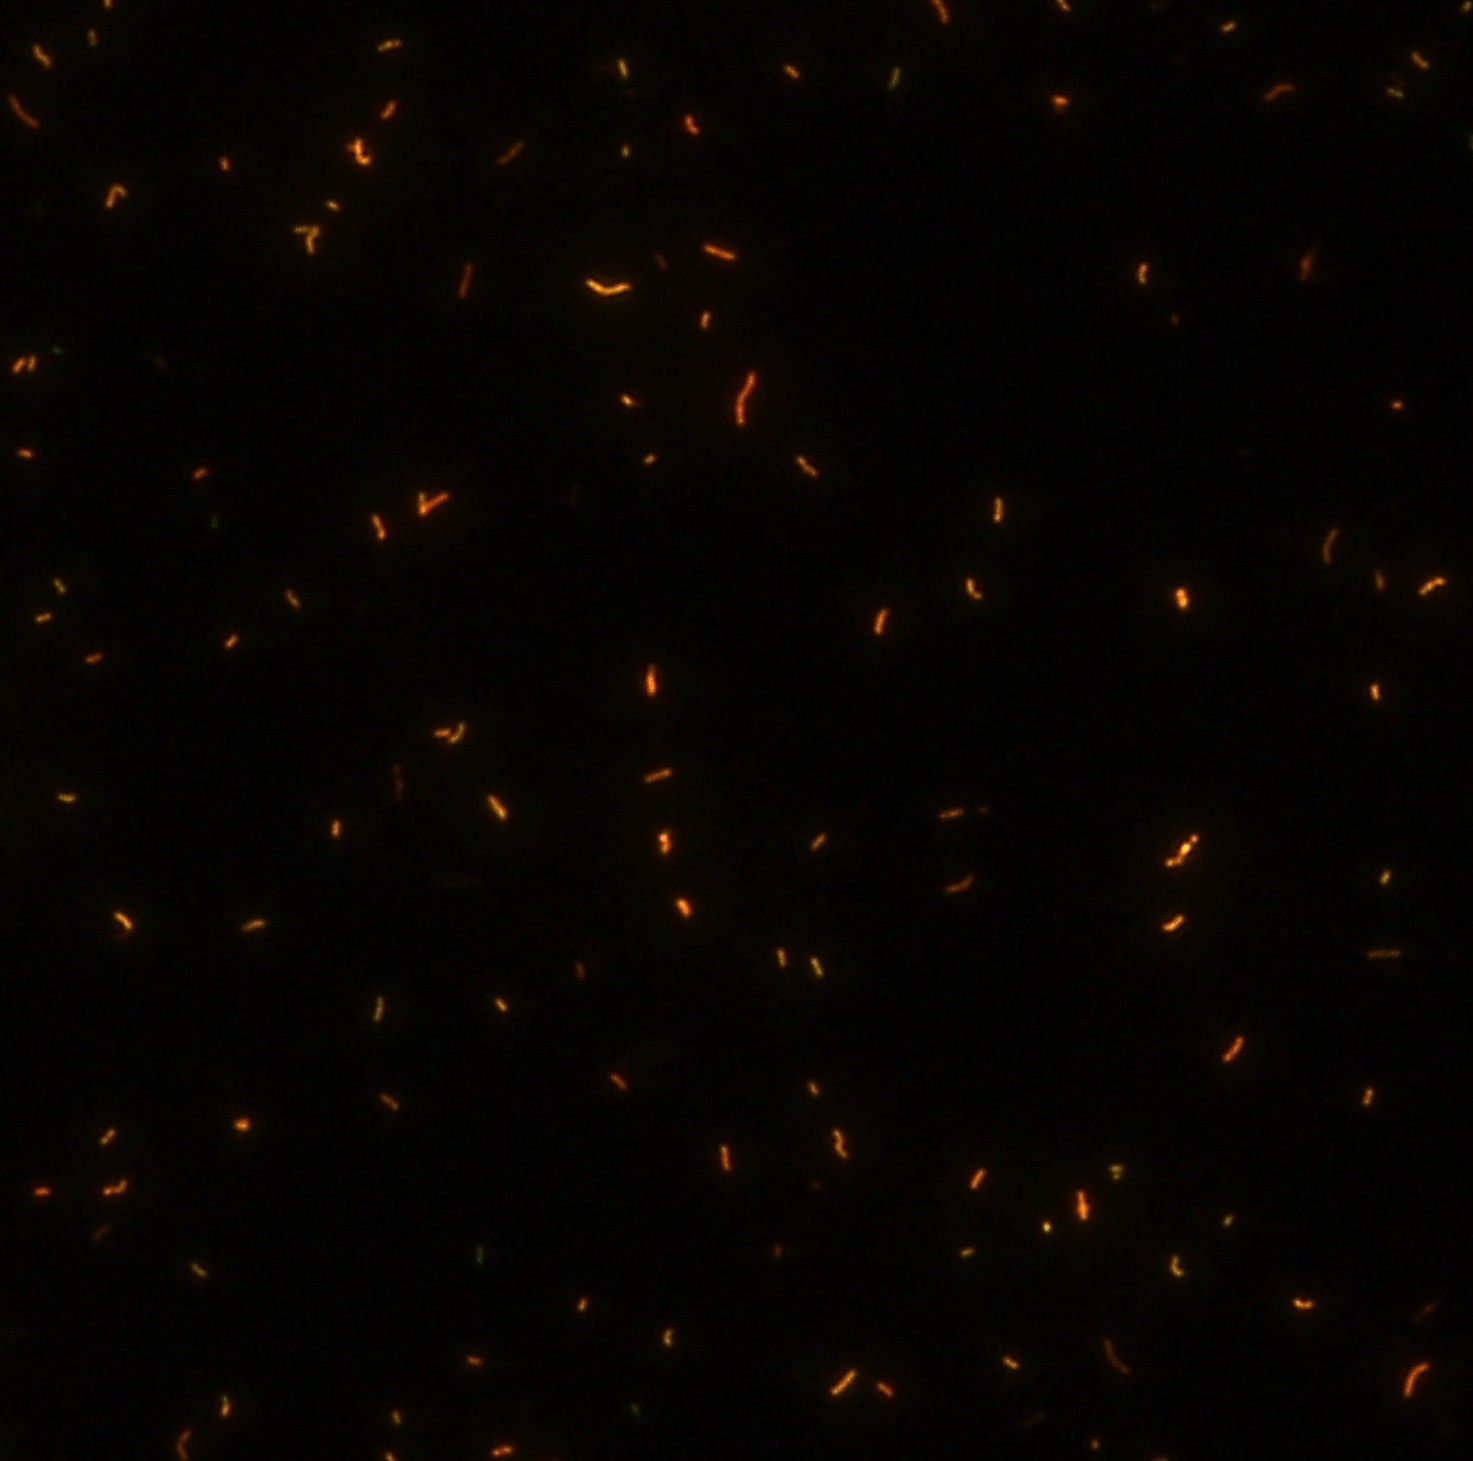

顯微染色技術(shù)是檢測結(jié)核桿菌方法之一。分枝桿菌細(xì)胞壁中含有分枝菌酸,其可以與染料牢固結(jié)合,具有“抗酸性”的特征。熒光染料金胺-羅丹明在染色中與抗酸生物細(xì)胞壁內(nèi)的分菌酸相結(jié)合,并耐受酸醇(脫色劑)清洗脫色。反染色劑高錳酸鉀被用來顯出染色生物。AFB(熒光)染色試劑盒設(shè)計既可用于染色機(jī),也可用于手工染色。產(chǎn)品穩(wěn)定性好,染色效果佳。

染色結(jié)果 熒光法×400

用于分枝桿菌、諾卡菌等細(xì)菌抗酸染色,包括熒光染色。